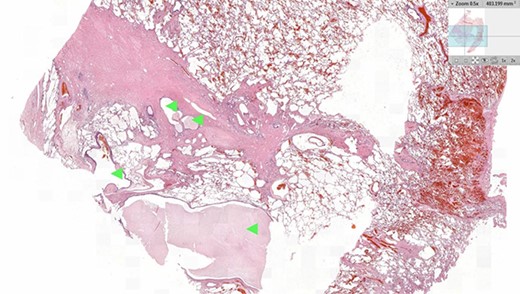

Histology of the specimen was undertaken to confirm the diagnosis. On sectioning, the lung parenchyma was extensively pneumonitic, and areas of fibrosis were identified surrounding blind and dilated bronchial spaces (Fig. 4). Haemorrhagic congestion with thickening of the vasculature was distributed within the fibrosed areas. Full histological analysis demonstrated changes consistent with BPS. Ultimately, no evidence of dysplasia or malignancy were found.

Histology image of the resected pulmonary section. Dilated bronchial spaces with mucous impaction can be identified (arrows).